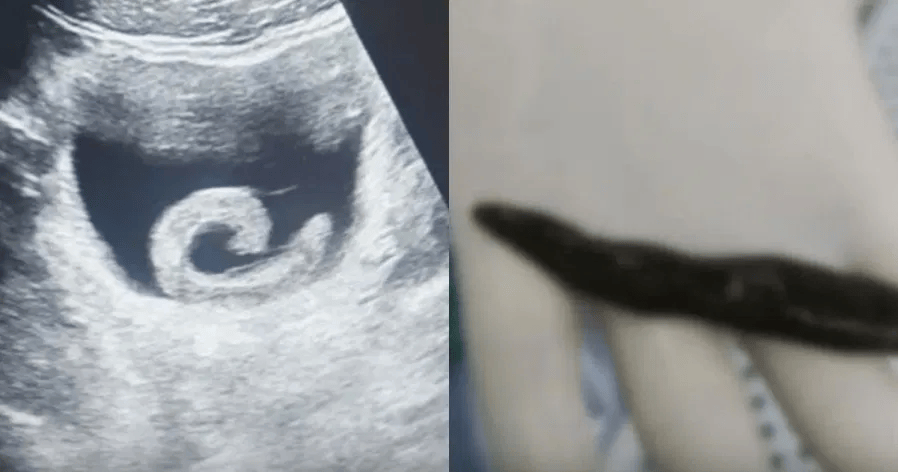

تعرض شاب صيني يبلغ من العمر 23 عاما لآلام شديدة، بعد أن جرب وصفة شعبية قرأ عنها على الإنترنيت، حيث قام بإدخال دودة حية بطول 5 سنتيمترات إلى مثانته عبر مجرى البول، اعتقادا منه بوجود «فوائد علاجية مذهـلة»!

تسببت الحية في انسداد مجرى البول، ما أدى إلى آلام حادة ومنع الشاب من التبول. ولم تتوقف المشكلة عند هذا الحد، إذ تحركت الحية داخل الجسم ووصلت إلى المثانة، حيث التصقت بجدارها وبدأت في إفراز مواد مضادة للتجلط، ما زاد من خطورة الحالة.

مع تفاقم الألم، توجه الشاب إلى قسم الطوارئ في أحد مستشفيات المدينة. تفاجأ الأطباء بالقصة، لكن فحص الموجات فوق الصوتية أكد وجود دودة حية داخل المثانة. على الفور، قرر الفريق الطبي إجراء جراحة طارئة لإنقاذ المريض.